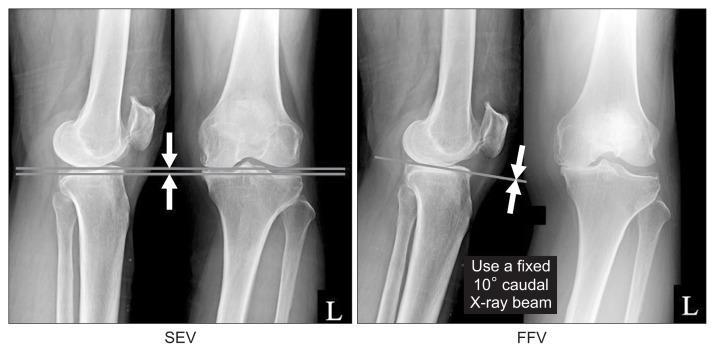

The fixed flexion view (FFV) of the knee is considered useful for evaluating the joint space when assessing the severity of osteoarthritis (OA) of the knee. To clarify the usefulness of FFV for evaluation of the joint space and severity of knee OA, this study evaluated changes in the joint space on the FFV and standing extended view (SEV) in patients with knee OA.

The SEV and FFV images were acquired in 567 patients (1,102 knees) who visited the hospital with a chief complaint of knee joint pain. Medial joint space width (MJSW) and Kellgren-Lawrence (K-L) classification assessed using the SEV and FFV images were compared.

Mean MJSW was significantly smaller when assessed on the FFV than on the SEV (3.02±1.55 mm vs. 4.31±1.30 mm; p<0.001). The K-L grade was the same or higher on the FFV than on the SEV.

The FFV is more useful than the SEV for evaluating the joint space in OA knees. Treatment strategies in patients with knee OA should be determined based on routinely acquired FFV images.